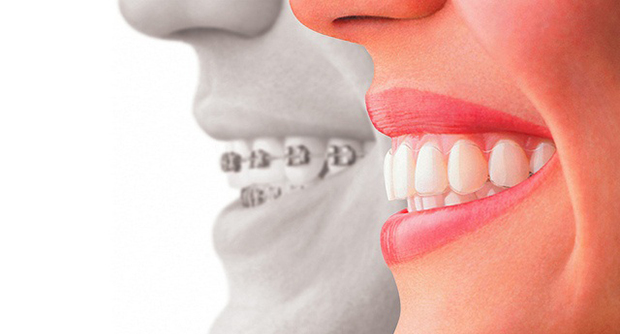

During your initial consultation, the adjacent teeth are examined to determine if they are strong enough to support a dental bridge. Any existing decay must be treated before proceeding. If the tooth is root canal filled, an X-ray is required to assess the success of the root filling. In some cases, inserting a post inside the root canal may be recommended to enhance the tooth’s support before receiving a dental bridge.

The dental bridge procedure typically requires two visits to complete.

During your initial visit, the shade for your future restoration is selected based on the neighbouring teeth’ colour to ensure a seamless match. Next, the selected abutments are reduced, which involves removing a calculated amount of tooth structure to create space for the crowns. Finally, an impression is taken, and your bite is recorded. This information will be sent to the dental lab for bridge fabrication.

During your second visit, the dental bridge is fitted and checked for colour matching, margin adaptation, and bite alignment with the opposing teeth. If everything is satisfactory, the dental bridge is fixed using strong cement.